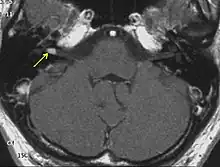

Diagnosis

NF2 is a genetically transmitted condition. Diagnosis is most common in early adulthood (20–30 years); however, it can be diagnosed earlier. NF2 can be diagnosed due to the presence of a bilateral vestibular schwannoma, or an acoustic neuroma, which causes a hearing loss that may begin unilaterally.[15] If a patient does not meet this criterion of diagnosis, they must have a family history of NF2, and present with a unilateral vestibular schwannoma and other associated tumors (cranial meningioma, cranial nerve schwannoma, spinal meningioma, spinal ependymomas, peripheral nerve tumor, spinal schwannoma, subcutaneous tumor, skin plaque). This being said, more than half of all patients diagnosed with NF2 do not have a family history of the condition.[15] Although it has yet to be included into clinical classification, peripheral neuropathy, or damage to the peripheral nerves, which often causes weakness, numbness and pain in the hands and feet, may also lead to a diagnosis of NF2. In children, NF2 can present with similar symptoms, but generally causes "visual disturbances (cataracts, hamartomas), skin tumors, mononeuropathhy (facial paresis, drop foot), symptomatic spinal cord tumors, or non-vestibular intracranial tumors".[15]

Bilateral vestibular schwannomas are diagnostic of NF2.[16]

- Detection of bilateral acoustic neuroma by imaging-procedures